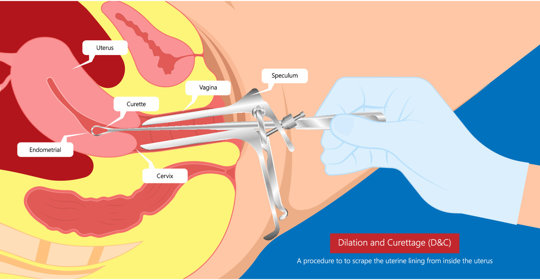

胎盤滯留宮腔:產後康復小知識,瞭解症狀及處理!